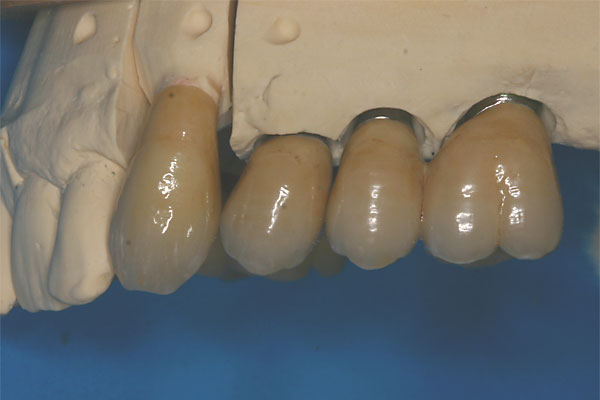

Metallkeramische, festsitzende Brücke |

FOTO Brücke Seitansicht |

FOTO vier kleine Brückensegmente ergeben die Oberkieferversorgung |